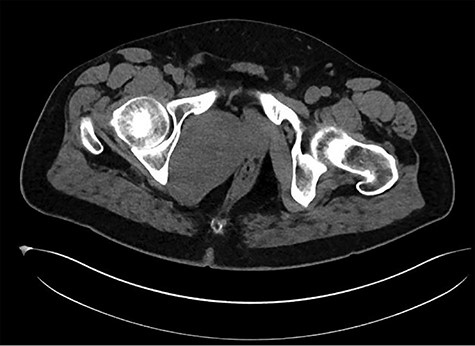

A healthy 47-year-old male with past medical history significant only for hypertension and nephrolithiasis presented to Englewood Health Medical Center in October 2019 with right flank pain radiating to the pubis, hematuria, hard stool with straining and fifteen pound weight loss over 6 months. On physical examination, multiple café au lait spots, small neurofibromas on his trunk and arms and axillary and inguinal freckling were observed. On CT scan, he was found to have a 10.1-cm soft tissue mass in the right hemipelvis and a nephroureteral stent with a 3-mm stone in the proximal right ureter (Fig. 1). Further history revealed the patient had a known pelvic mass discovered on CT approximately 10 years prior (Fig. 2), which was again observed on CT in June 2019 during a hospitalization for nephrolithiasis at Hackensack University Medical Center (Fig. 3); he had been lost to follow-up.

EHMC 10/21/19: 10.0 × 6.5 × 7.5-cm-sized right pelvic wall soft tissue mass.